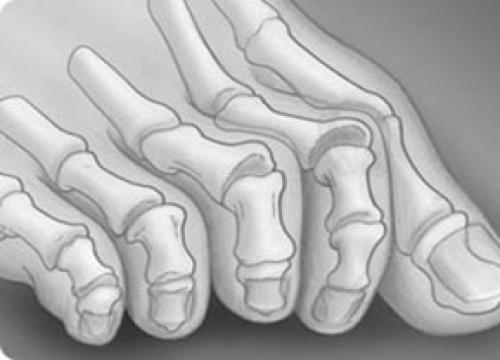

Стопа портного (деформация Тейлора, варусная деформация пятого пальца стопы, косточка на мизинце) – возвышение в области основания 5 пальца стопы, связанное с разрастанием головки пятой плюсневой кости и её отклонением кнаружи.

По своей природе стопа портного схожа с вальгусной деформацией первого пальца стопы, однако встречается значительно реже. Почему же она называется стопой портного? Это название появилось ещё во времена средневековья, когда портные и их подмастерья были вынуждены длительное время сидеть со скрещенными ногами.

Основными критериями для установления диагноза стопы портного являются формирование костного возвышения по наружной поверхности головки пятой плюсневой кости, увеличение 4-5 межплюсневого угла (в норме 6-8°), увеличение угла наружного отклонения 5 плюсневой кости (в норме до 7°), увеличение ширины головки 5 плюсневой кости, формирование мозоли по наружной поверхности основания 5 пальца стопы.

1 | К 1 типу относят увеличение ширины головки 5 плюсневой кости |

2 | Ко 2 типу относят врождённое искривление 5 плюсневой кости с нормальным межплюсневым углом. |

3 | К 3 типу (наиболее часто встречаемому) относится увеличение межплюсневого угла. |